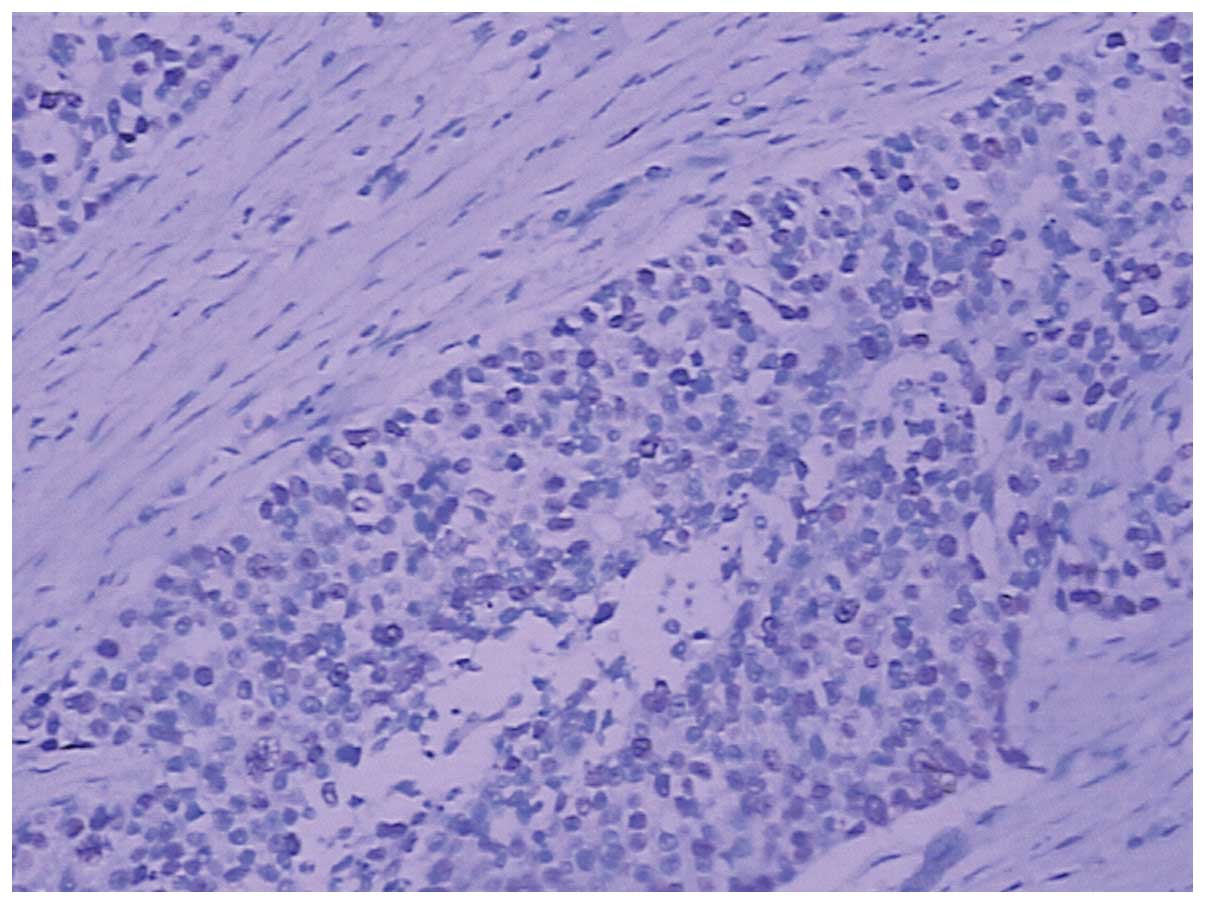

Histopathology revealed that the SCC infiltrated into the serosal fibrous tissue, lamina muscularis and submucosa of the gastric wall (Fig. 3A–C); however, there was no cancer cell infiltration into the mucosa. The surgical margins were negative, however, metastasis to one lymph node in the lesser curvature of the stomach was observed. Furthermore, the esophagogastric junction was negative for the tumor. The immunohistochemical staining was positive for cytokeratin (CK)5/6, p63, CKpan and glutathione S-transferase π (Figs. 4–7), and negative for cluster of differentiation (CD)56, CDX-2, chromogranin A, CK20, CK7, S100, Syn, Villin, P-glycoprotein, epidermal growth factor receptor, topoisomerase II and p53. The Ki-67 proliferation index was ~50% (Fig. 8). Due to the progression of the disease, postoperative chemotherapy was recommended, and the patient and the patient’s family consented to four sessions of chemotherapy. At the end of the 12-month follow-up, which was conducted using ultrasonography and CT, the patient had survived and there was no evidence of recurrence and metastasis.

Figure 3

Tumor cells were observed in the (A) gastric serosa fibrous tissue, (B) lamina muscularis and (C) submucosa. (Hematoxylin and eosin staining; magnification, ×100).

Figure 4

Strong expression of cytokeratin 5/6 observed via immunohistochemical staining. (Hematoxylin and eosin staining; magnification, ×200).